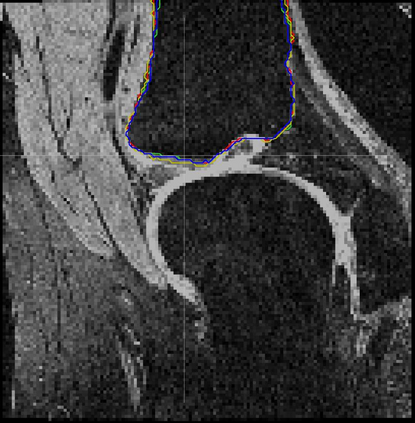

Direct automatic segmentation of objects from 3D medical imaging, such as magnetic resonance (MR) imaging, is challenging as it often involves accurately identifying a number of individual objects with complex geometries within a large volume under investigation. To address these challenges, most deep learning approaches typically enhance their learning capability by substantially increasing the complexity or the number of trainable parameters within their models. Consequently, these models generally require long inference time on standard workstations operating clinical MR systems and are restricted to high-performance computing hardware due to their large memory requirement. Further, to fit 3D dataset through these large models using limited computer memory, trade-off techniques such as patch-wise training are often used which sacrifice the fine-scale geometric information from input images which could be clinically significant for diagnostic purposes. To address these challenges, we present a compact convolutional neural network with a shallow memory footprint to efficiently reduce the number of model parameters required for state-of-art performance. This is critical for practical employment as most clinical environments only have low-end hardware with limited computing power and memory. The proposed network can maintain data integrity by directly processing large full-size 3D input volumes with no patches required and significantly reduces the computational time required for both training and inference. We also propose a novel loss function with extra shape constraint to improve the accuracy for imbalanced classes in 3D MR images.